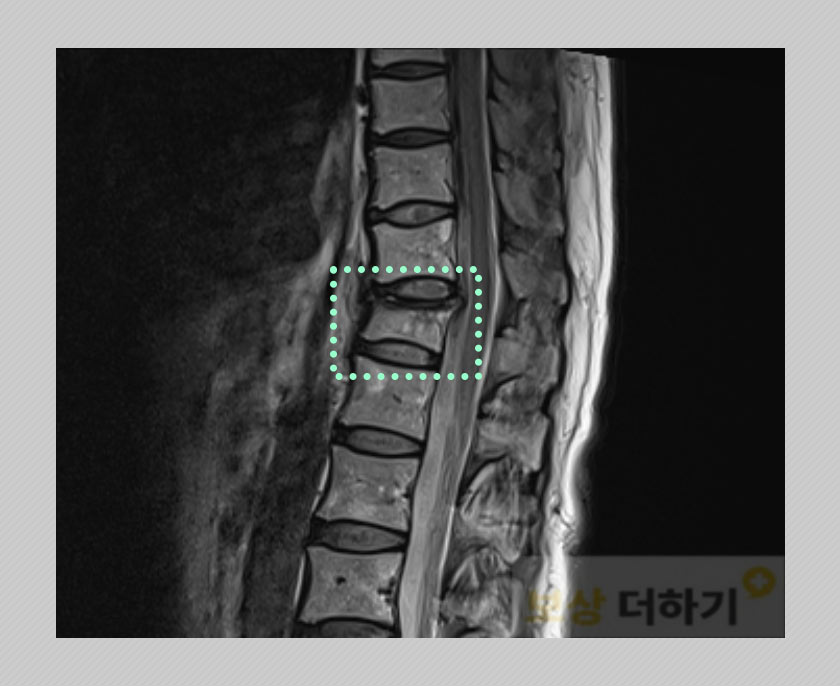

▤ 흉추 12번 (T12) 골절 엑스레이 상으로 골절 소견이 있어 MRI 촬영으로 더 자세한 검사를 하였습니다. 다행히 당장 수술이 필요하진 않다는 주치의의 말씀에 따라 보존 치료를 하셨어요. (* 많은 경우 비수술 치료를 하며, 상태에 따라 유합술이나 골시멘트술이 행해지는 경우가 있습니다.)

또한 흉추 압박 골절 비수술의 경우 압박률, 척추가 휘어지는 정도에 따라 보험약관에서 인정하는 장해 지급률이 정해지기 때문에 이에 대해 올바른 측정 역시 중요했습니다. 청구 전 준비부터 실제 지급까지 저희는 최선을 다해 도움드렸습니다.